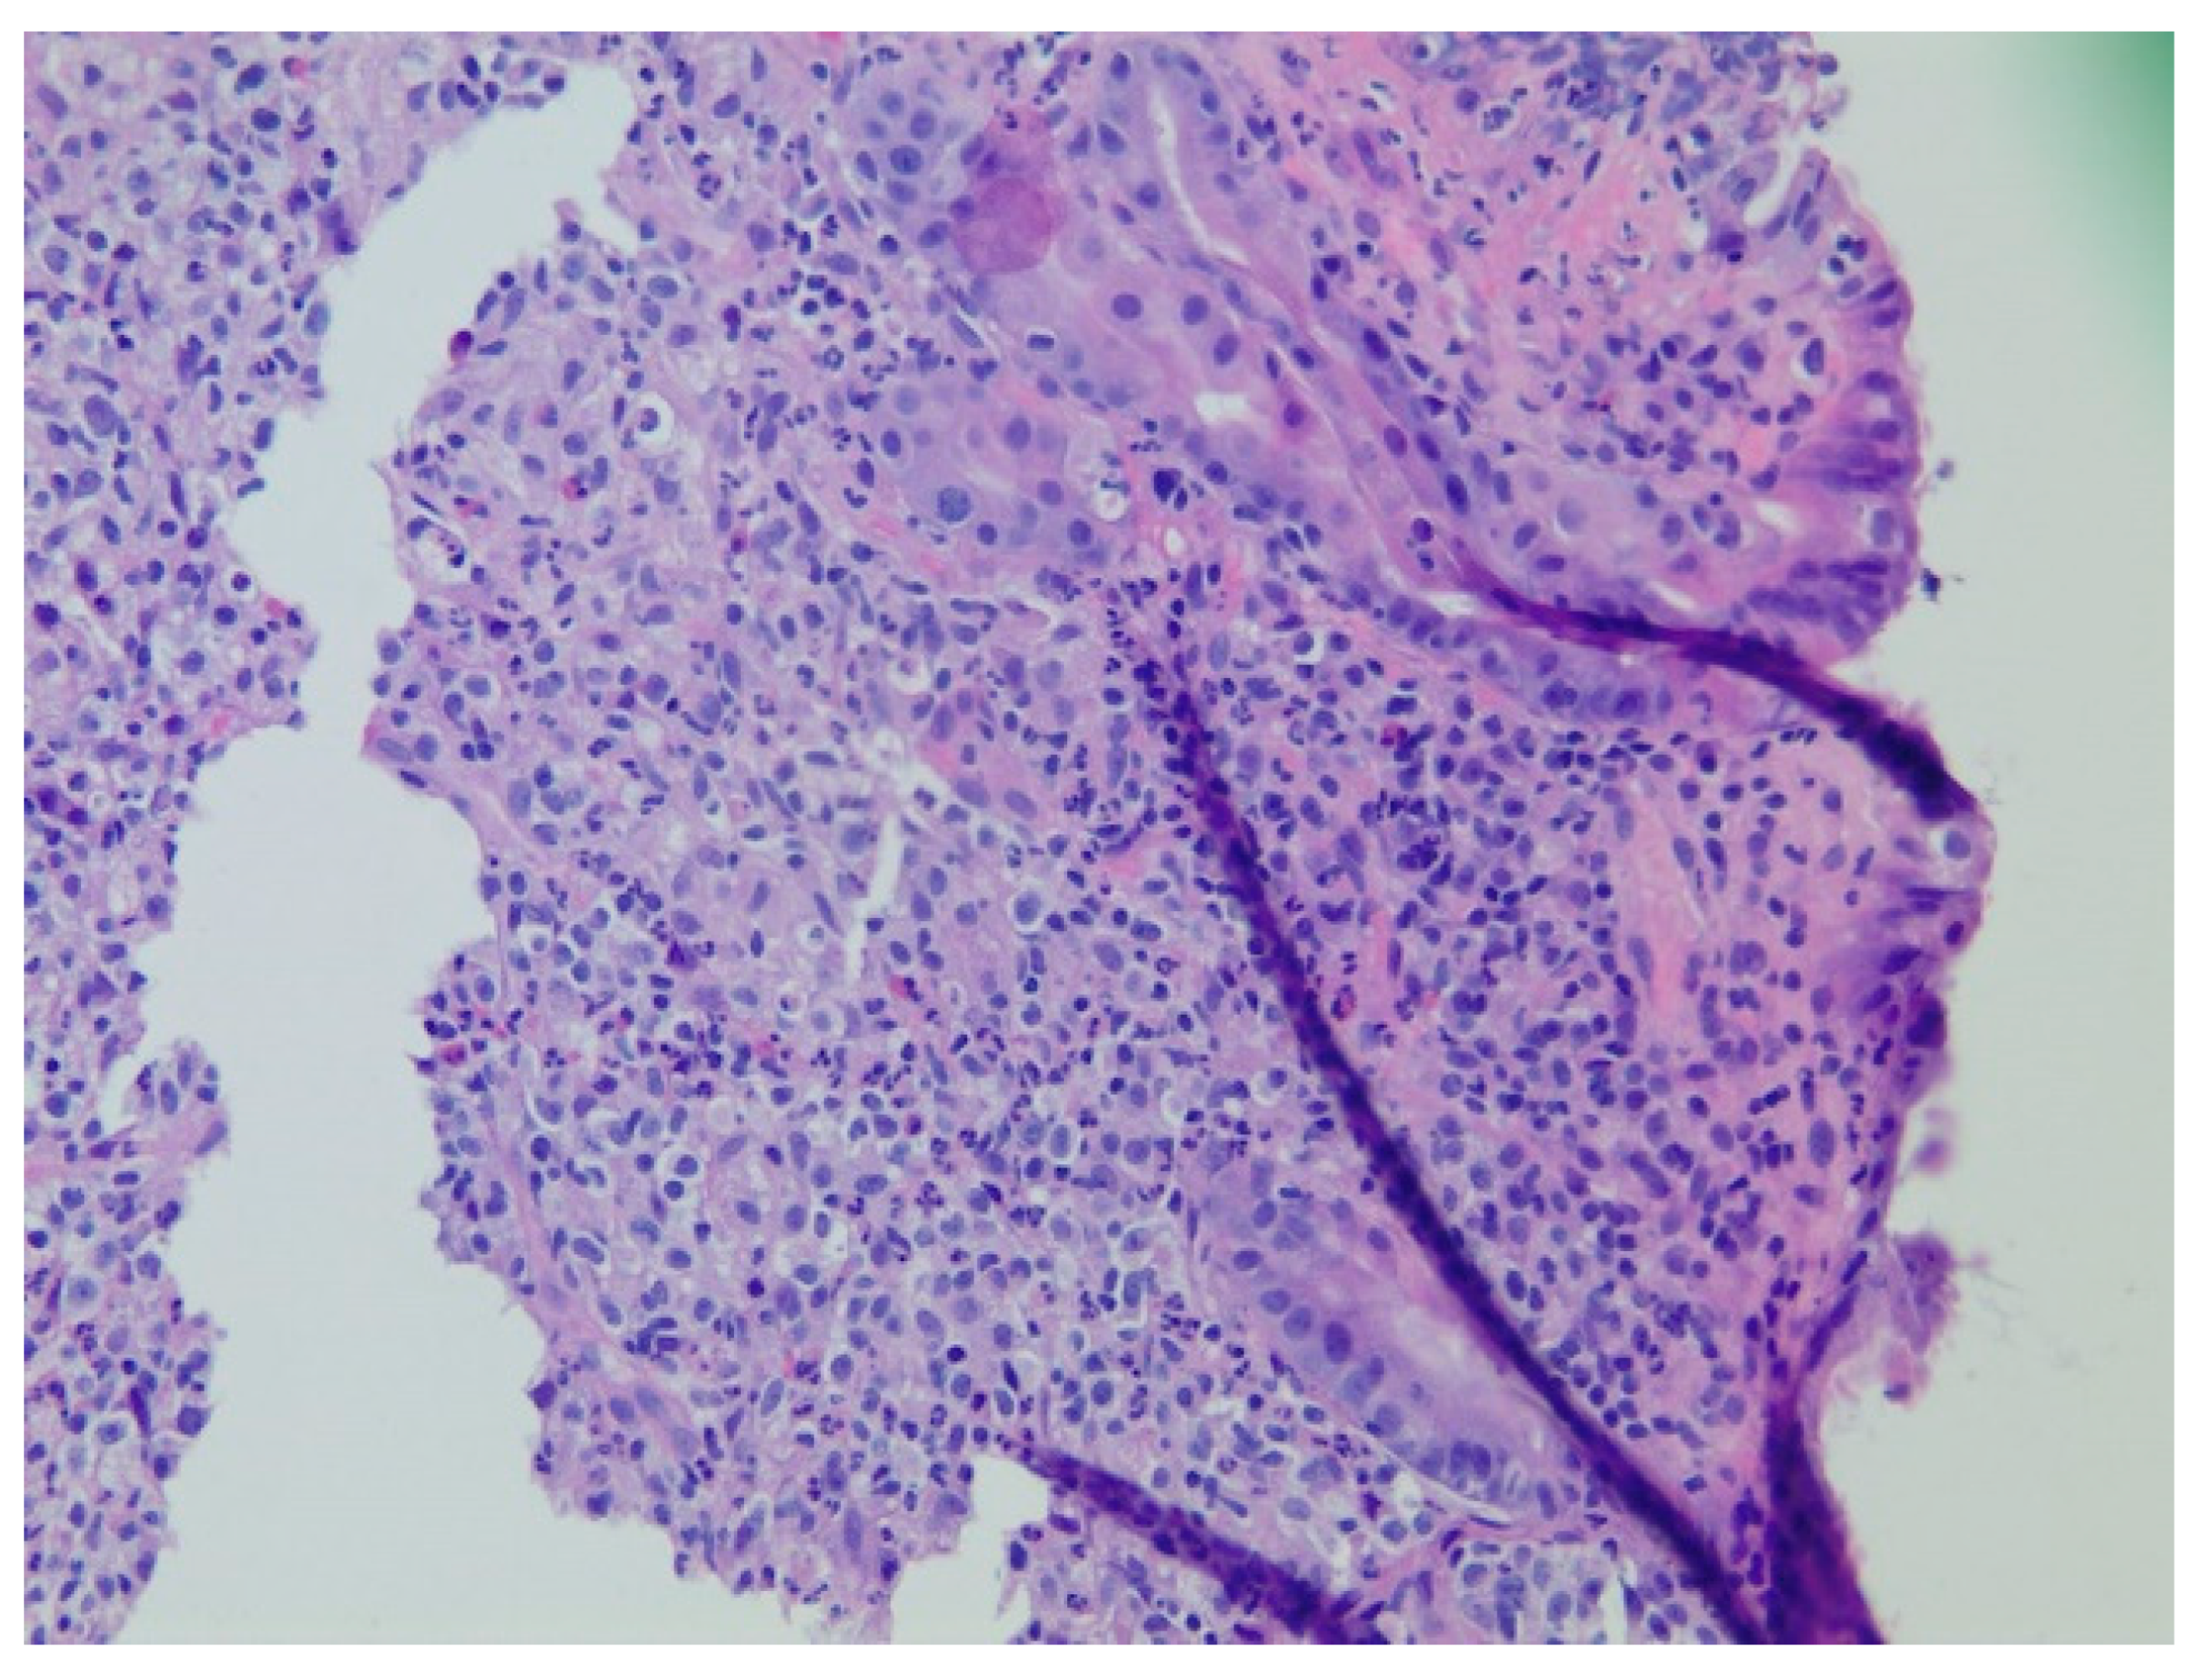

| 2 | M | 84 | Lymphoid | Fundus and cardia | Ulcerated and necrotic mass | Liver, urinary bladder | Diffuse large B-cell lymphoma | None | Death in 2 months after EGD diagnosis of metastasis |

| 3 | F | 35 | Lung | Fundus | Fungating mass | Esophagus, mediastinum | Large-cell neuroendocrine carcinoma | Chemotherapy-carboplatin/ etoposide | Death 1 month after EGD diagnosis of metastasis |

| 4 | F | 73 | Kidney | Fundus and body | Multiple large friable masses | Liver and lungs | Clear cell renal carcinoma | Nephrectomy, chemotherapy, immunotherapy (Axitinib) | Death 10 days after EGD diagnosis of metastasis |

| 5 | M | 76 | Lung | Body | Cratered ulcers | Liver, bone and adrenals | Small cell carcinoma (poorly differentiated neuroendocrine Ca) | None | Death 7 days after EGD diagnosis of metastasis |